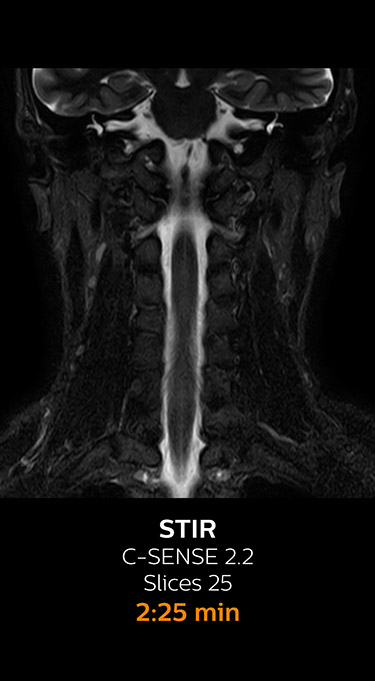

Fast MRI of cervical spine

With Compressed SENSE, the scan time for the routine cervical spine examination at KNC was reduced from 13:11 to 9:52 minutes, which corresponds to 25% reduction.

MRI examination of cervical spine with Compressed SENSE

MRI examination of the cervical spine with Compressed SENSE

Ingenia 3.0T CX

Scan time 9:52 min. (was 13:11 min. without Compressed SENSE)